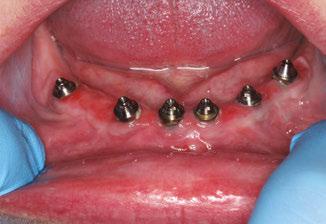

Figures 1A and 1B: 1A. Pre-extraction records. Patient presented with periodontal con cerns and extensive decay. 1B. Six LOCATOR® Implants (Zest Dental Solutions) were placed in strategic positions for a future fixed-prosthesis option

Interim dentures were fabricated prior to the extractions. All remaining teeth were removed, alveoloplasty performed, and implants placed at the same appointment. The interim dentures were inserted immediately after surgery with a tissue-condi tioning reline material. The patient was allowed to heal for 4 months, then the implants were successfully tested for osse ointegration. LOCATOR abutments were selected and torqued as

12 Implant Practice US Volume 15 Number 4 CASE REPORT

recommended by the manufacturer prior to beginning the definitive prosthetic treatment. Maxillary and man dibular implant-retained overdentures were fabricated using traditional indirect techniques. Both prostheses included metal frameworks for strength and long-term survival, and the LOCATOR housing was picked up chairside at the time of delivery.